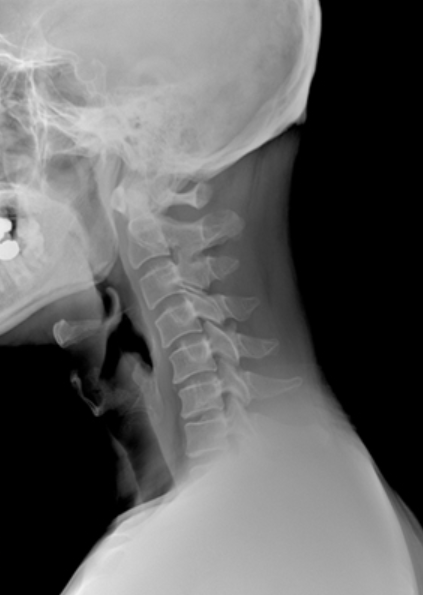

일자목 개선

C 모양으로 살짝 튀어나와 곡선을 유지해야 하는 경추뼈가

C 모양에서 일자 형태로 바뀌는 질환입니다.

일자목은 정상적인 곡선이 없이 뻣뻣하기 때문에 목에 더해지는 충격을 그대로 받게 됩니다.

그러므로 정상적인 사람보다 목 디스크 발생 위험이 높기에 초기에 개선해야 합니다.